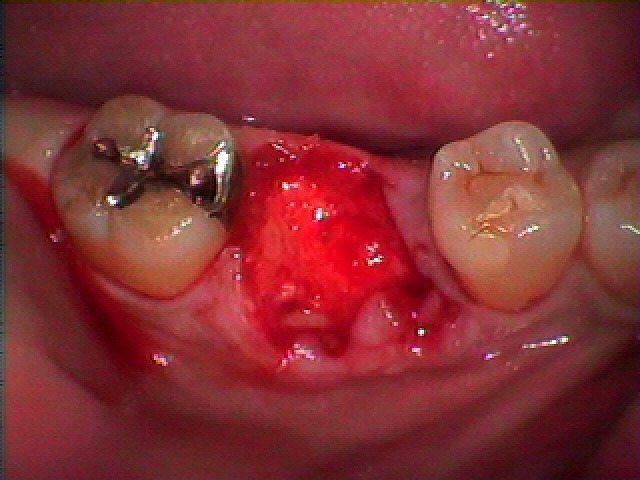

右下の6番部の抜歯即時インプラント埋入 インプラント治療の臨床現場 40代男性|お知らせ |広島市安佐南区の歯科医院 右下の6番部の抜歯即時インプラント埋入 インプラント治療の臨床現場 40代男性 トップ お知らせ・ブログ お知らせ 右下の6番部の抜歯即時インプラント埋入 インプラント治療の臨床現場 40代男性 右下の6番部の抜歯即時インプラント埋入 インプラント治療の臨床現場 40代男性 ずっとほったらかしにしていた歯になります 保存不能な状態 抜歯を行っていきました インプラント窩を形成 インプラント埋入を行っていきます 骨補填材を転入していきました 縫合して終了となります 術前のCTになります 術前術後のCTになります 術前術後のパノラマになります Web診療予約 初めての方へ 選ばれ続ける理由 院内設備について 歯が痛いしみる一般歯科 歯がぐらぐらする歯周病 健康な歯を保ちたい予防歯科 子供の虫歯予防をしたい小児歯科 銀歯をセラミックに審美歯科 白い歯を目指しませんか?ホワイトニング 矯正専門医がいるので安心矯正歯科 抜けた歯を補いたいインプラント・入れ歯 医院案内 スタッフ紹介 メリィハウス歯科クリニックオフィシャルホームページ ラベンダー歯科クリニックオフィシャルホームページ お知らせ・ブログ ホーム 診療科目 一般歯科 歯周病治療 予防治療 小児歯科 審美治療 ホワイトニング 矯正歯科 入れ歯・インプラント マウスピース矯正 初めての方へ 院長・スタッフ 設備紹介 医院案内・アクセス メニューを閉じる